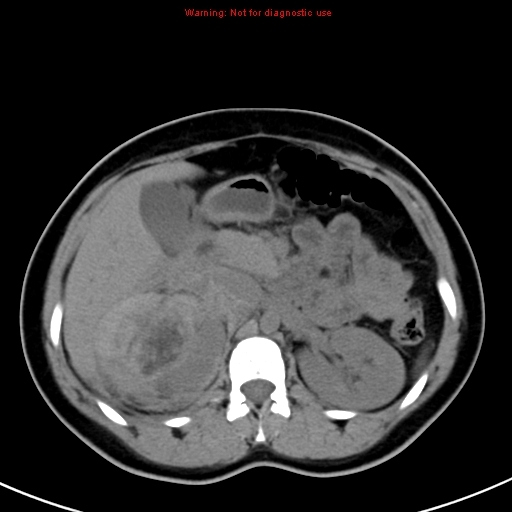

Angiomyolipoma (Aml)

Case courtesy of Dr Behrang Amini, Radiopaedia.org, rID: 35925

Axial CT through the kidneys shows a fat-attenuation lesion in the left kidney with a perirenal collection, most likely blood. This is consistent with a bleeding angiomyolipoma.